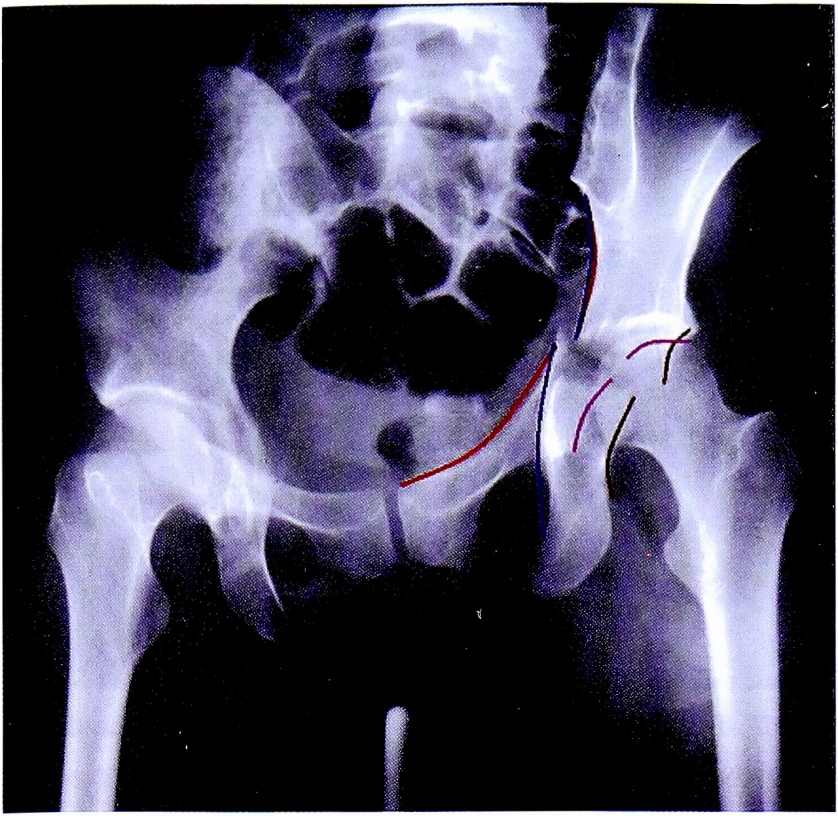

Таким образом, методом исключения неповрежденных структур вертлужной впадины, диагностирован перелом задней колонны вертлужной впадины. Повреждение подвздошно-седалищной линии и деформация контуров запирательного отверстия подтверждает этот диагноз (рис. 28). На рентгенограмме в косой запирательной проекции определяется задний вывих головки бедренной кости и отсутствие отдельного фрагмента задней стенки (рис. 29).

Рис. 28. Верификация перелома задней колонны.

Fig. 28. Verification of posterior column fracture.

Рис. 29. Рентгенограмма в косой запирательной проекции.

Fig. 29. Obturetor oblique view.